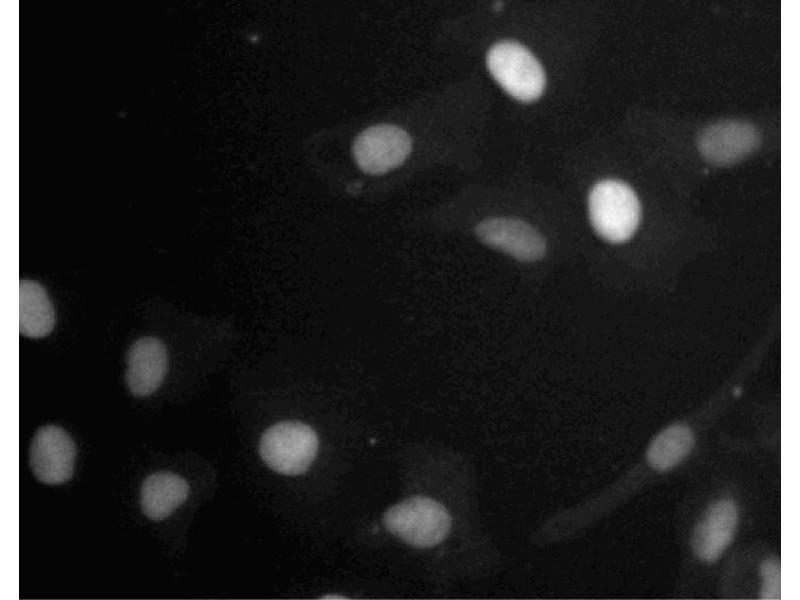

Bioimaging

1. Seed the cells in appropriate culture medium at ~10,000 cells per well in an 96-well Imaging Plate and culture overnight.

2. Remove the culture medium from the wells, and fix the cells by adding 100 myl of Fixation Buffer to each well. Incubate for 10 minutes at room temperature (RT).

3. Remove the fixative from the wells, and permeabilize the cells using either 90% methanol, or Triton™ X-100: a. Add 100 myl of -20°C 90% methanol to each well and incubate for 5 minutes at RT. OR b. Add 100 myl of 0.1% Triton™ X-100 to each well and incubate for 5 minutes at RT.

4. Remove the permeabilization buffer, and wash the wells twice with 100 myl of 1× PBS.

5. Remove the PBS, and block the cells by adding 100 myl of to each well. Incubate for 30 minutes at RT.

6. Remove the blocking buffer and add 50 myl of the optimally titrated primary antibody (diluted in Stain Buffer) to each well, and incubate for 1 hour at RT.

7. Remove the primary antibody, and wash the wells three times with 100 myl of 1× PBS.

8. Remove the PBS, and add the second step reagent at its optimally titrated concentration in 50 myl to each well, and incubate in the dark for 1 hour at RT.

9. Remove the second step reagent, and wash the wells three times with 100 myl of 1× PBS.

10. Remove the PBS, and counter-stain the nuclei by adding 200 myl per well of 2 myg/ml Hoechst 33342 in 1× PBS to each well at least 15 minutes before imaging.

11. View and analyze the cells on an appropriate imaging instrument.